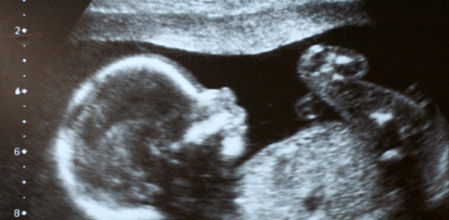

Durante el embarazo, la rotura de la bolsa amniótica, conocida comúnmente como “romper aguas”, es un signo claro de que el nacimiento del bebé está cerca. Sin embargo, no siempre es fácil distinguir este hecho de otras posibles fuentes de humedad, como pérdidas de orina. Es de vital importancia identificar si se ha producido una pérdida de líquido amniótico, para ello nos hacemos eco de la opinión profesional sobre maternidad y salud de referentes como Natalben y iNatal.